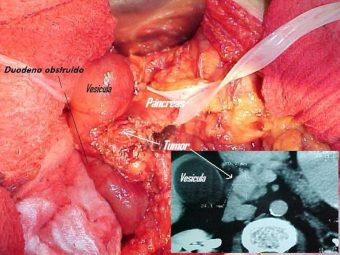

Pancreatitis, quiste y tumor

Envíado por Dr. Carlos Edgardo Escobar